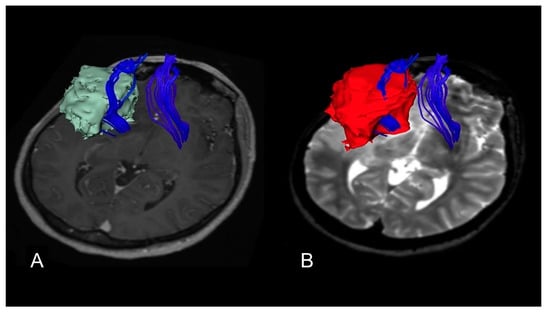

4.3. Volumetric Analysis